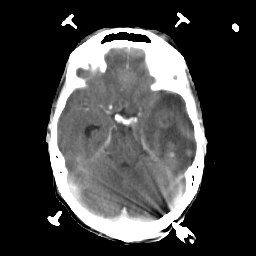

Metastatic bronchogenic carcinoma: Roentgen-ray CT -- Slice #7

[Home][Help][Clinical] Slice 7